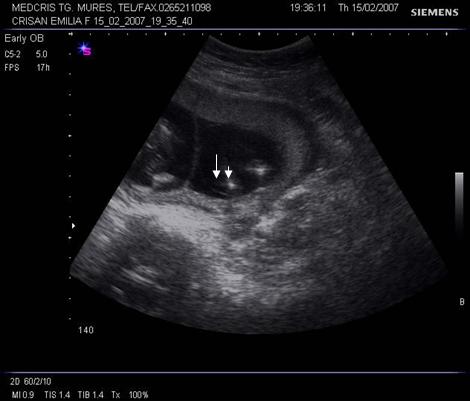

Fig nr 37. Aceeasi sarcina gemelara de 6 sapt., sectiune fara embrioni,cu sacii amniotici caracteristic dispusi in ochi de bufnita